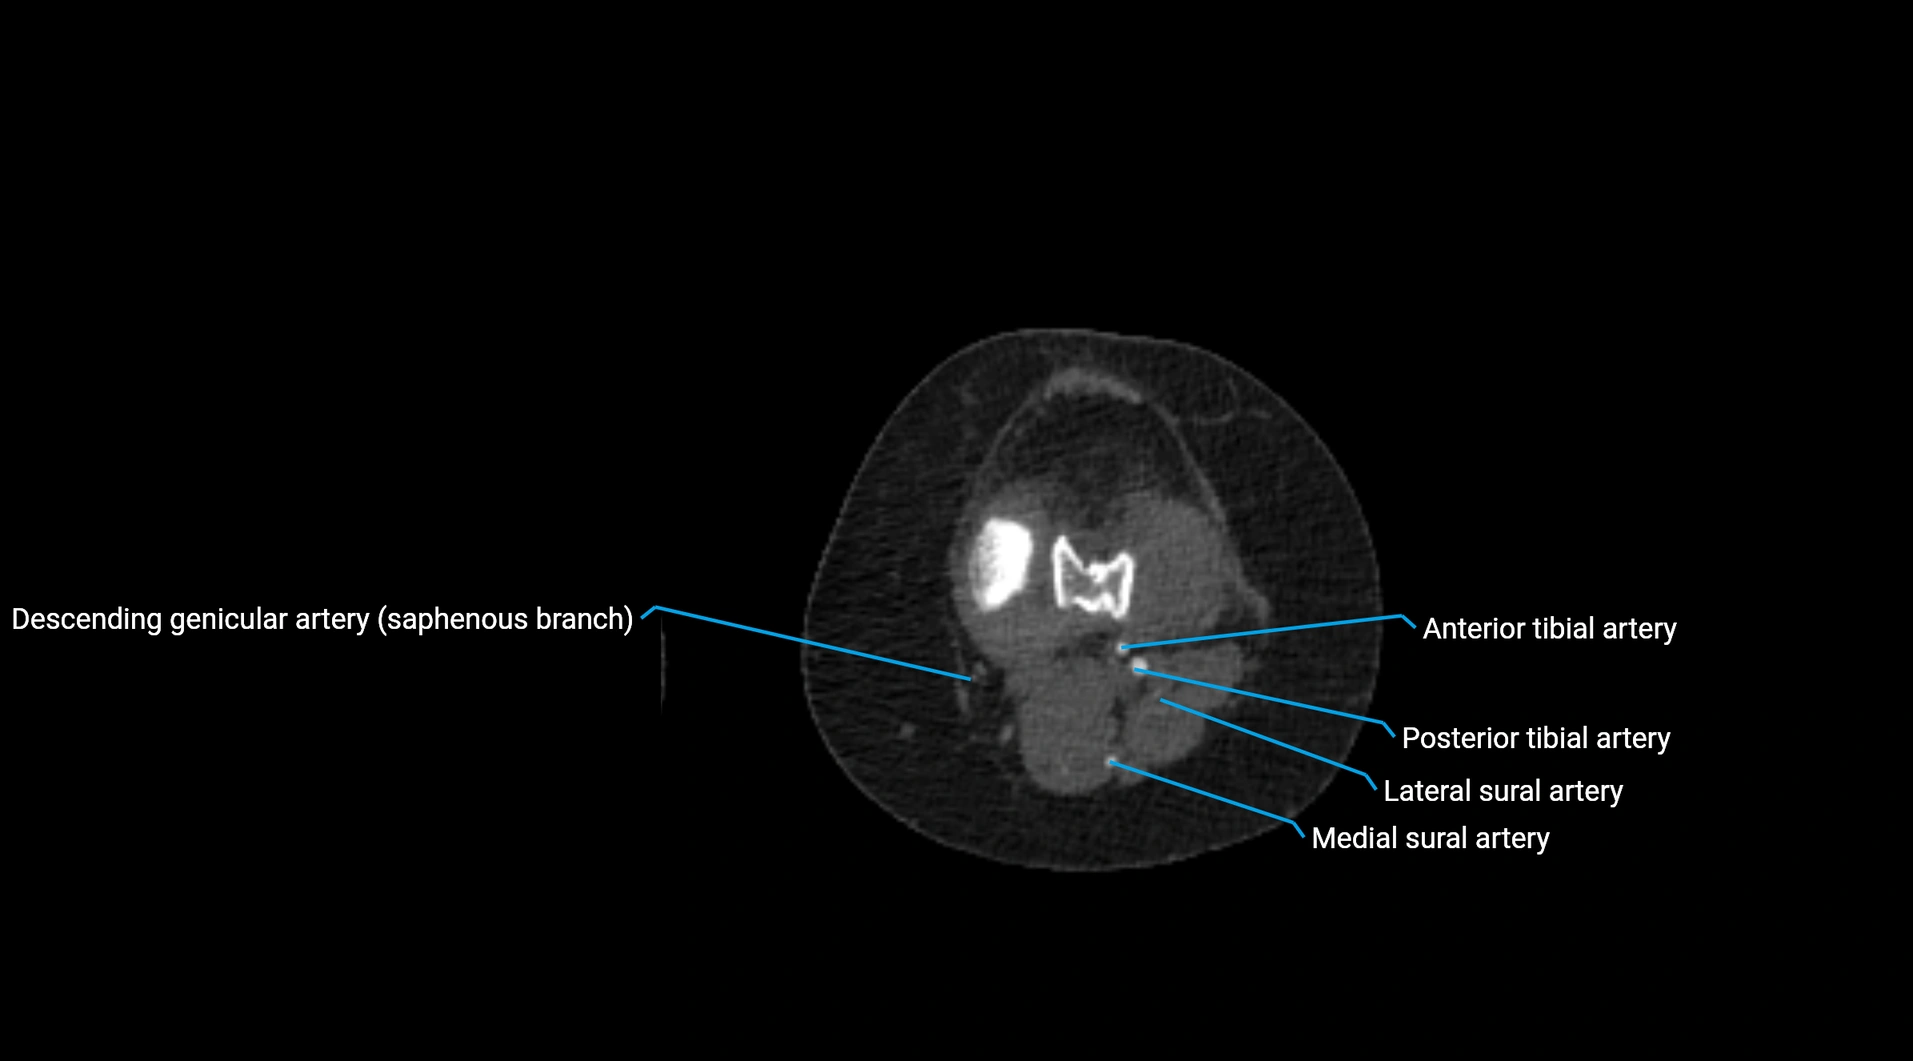

Contrast-enhanced CT (CTA):

• Gold standard for abdominal aortic imaging

• Provides excellent detail of lumen, wall, aneurysm, thrombus, and branch vessels

• Multiplanar and 3D reconstructions help in aneurysm measurement, stent graft planning, and dissection evaluation